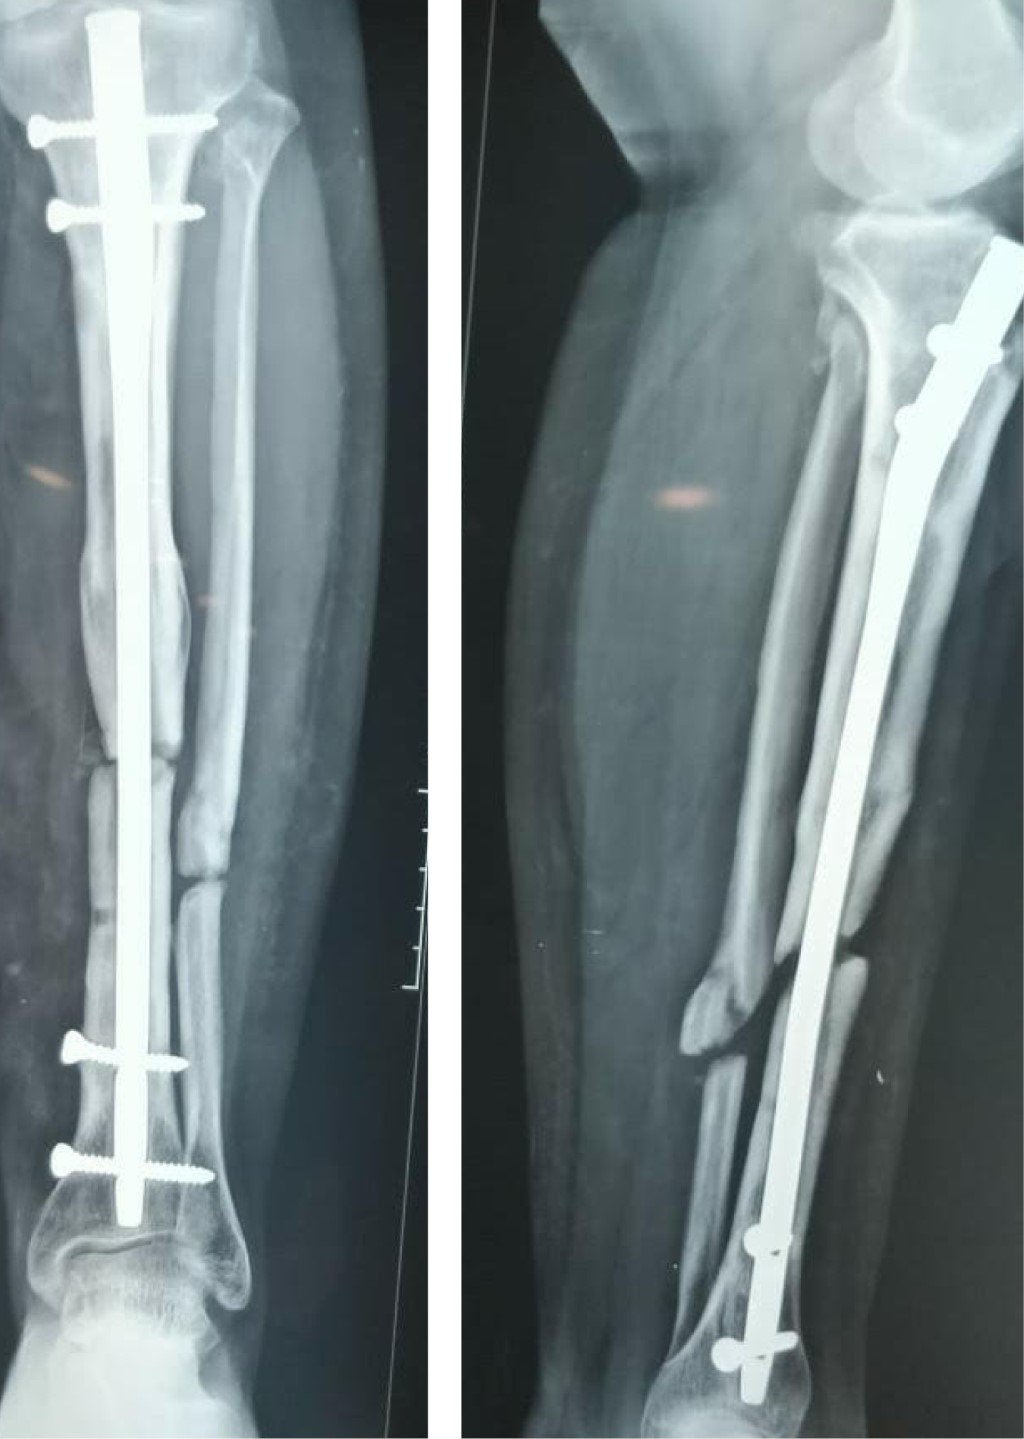

A las cuatro semanas posteriores se realiza el seguimiento sin datos de complicaciones postquirúrgicas, con cita a tal efecto en cuatro semanas con radiografía AP y lateral de pierna, en donde se observa una conveniente colocación de injerto, se realizan citas de verificación cada dos meses con radiografías de control; a los seis meses se perciben datos de consolidación acorde a la técnica, integrando puentes óseos en al menos tres corticales y exhibiendo marcha sin dolor (Figura 4), por lo que se inicia marcha asistida con bota larga tipo walker que deriva tolerada, la cual se retira a los dos meses.

Figura 4